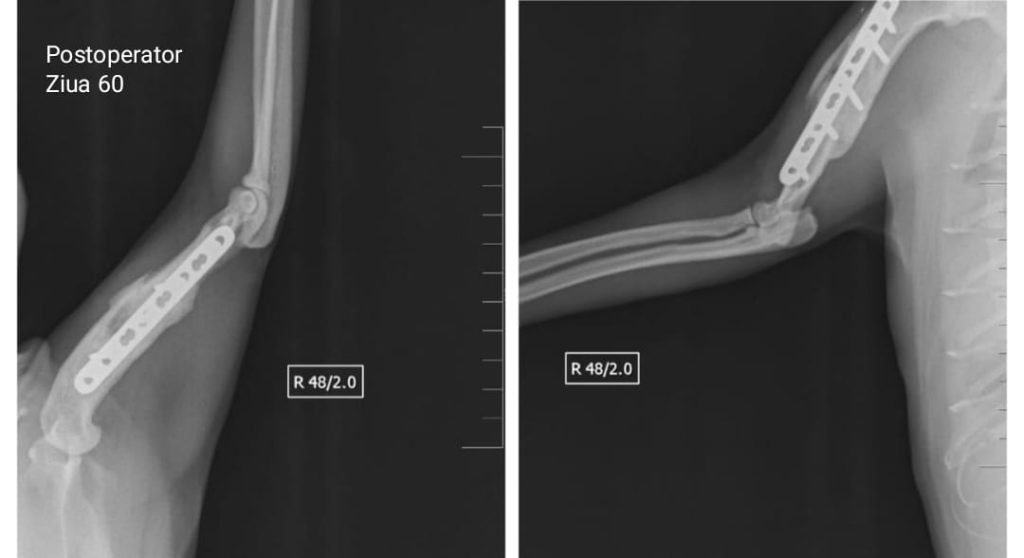

Fractură de humerus produsă prin împușcare, un tip de traumatism sever care necesită o abordare chirurgicală complexă și un protocol atent de monitorizare. Radiografiile realizate înainte de operație au evidențiat traiectul proiectilului și zonele cu pierdere osoasă, permițând planificarea exactă a intervenției.

Stabilizarea a fost realizată cu implanturi ortopedice dedicate, iar imaginile postoperatorii confirmă obținerea unei alinieri corecte și a unei fixări stabile. Evoluția pacientului a fost urmărită radiologic de-a lungul procesului de vindecare, observându-se formarea progresivă a calusului și consolidarea completă a osului.

După confirmarea vindecării osoase, implanturile au fost extrase pentru a elimina orice risc de complicații pe termen lung.

Pacientul s-a recuperat integral, fără sechele funcționale, recăpătându-și mobilitatea și confortul. Acest caz subliniază importanța unei intervenții rapide, a unui protocol chirurgical modern și a unei monitorizări riguroase în traumatologia severă.